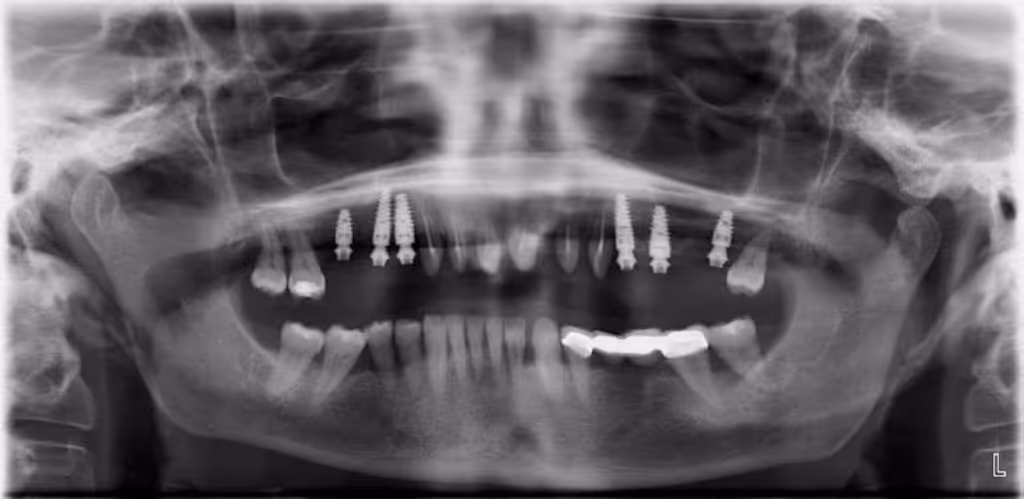

La pérdida de piezas dentarias en el maxilar superior, especialmente en la zona posterior, representa un desafío funcional y estético que se complica por el desgaste progresivo de los dientes anteriores. En el caso clínico presentado, se optó por una rehabilitación integral que incluyó la colocación de implantes osteointegrados en premolares y molares, junto con la preparación de los dientes anteriores para la colocación de coronas fijas.